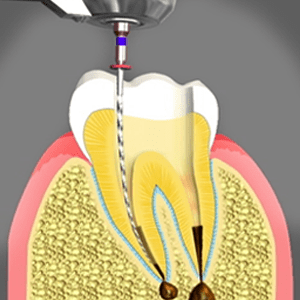

Root Canal Treatment

Root canal is so popular in the field of endodontics that at times an endodontic treatment is used as a synonym to mean the other. Pulp forms the core of natural tooth. Tooth decay and injury can open up way for bacteria to reach the pulp of the tooth. An infected pulp can cause serious problems in oral health. Root canal treatment is performed to remove the infected pulp and fill the area with appropriate material. Gutta-percha and core build up material are used in order to protect the natural tooth. Root canal process is performed by endodontists and experienced dentists. Local anaesthesia is used during the procedure for painless treatment.